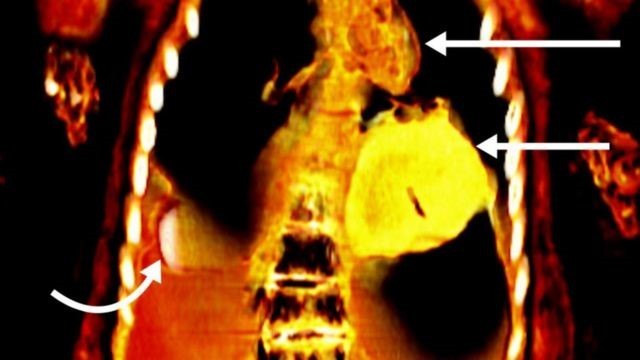

O cadáver do chamado ‘menino de ouro’ foi descoberto em 1916, mas não havia sido examinado em detalhes até agora. Imagem de tomografia mostra o coração de ouro da múmia

As imagens obtidas revelaram que o corpo tinha 49 amuletos de 21 tipos diferentes, muitos deles feitos de ouro. Por isso, a múmia foi batizada como o “menino de ouro”, anunciou Saleem em artigo publicado na revista Frontiers in Medicine.

As imagens mostraram que sob as mortalhas que cobriam o corpo do jovem havia um objeto ao lado do pênis, uma língua dourada dentro da boca e um objeto em forma de coração, também feito de ouro, abaixo da cavidade torácica.